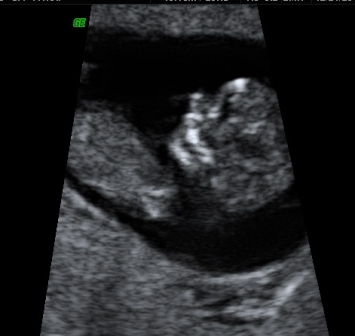

first u/s & NT scan

I had my first u/s and NT scan today. It was well worth the wait! My LO was measuring right on target. LO would not cooperate however, and kept covering its eyes with its hands. Nevertheless, I am in LOVE! All the measurements were perfect so we are at the lowest risk. I am so excited!

I forgot to add - I am 11w3d Image Attachment(s):